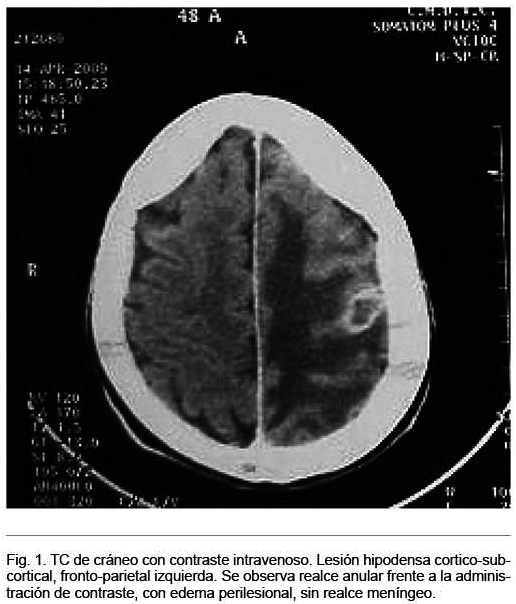

Mujer de 45 años, ocupación en labores, diabética tipo 2 de reciente diagnóstico. Procedente de Treinta y Tres. Ingresó por cuadro clínico progresivo de varios meses de evolución de paresia e hipoestesia braquial derecha, agregó en la evolución crisis epilépticas parciales simples de dicho miembro. Sin elementos de hipertensión intracraneana. En la exploración física se destacó paresia e hipoestesia braquial derecha a predominio distal, siendo el resto de la exploración normal. La tomografía computada (TC) de cráneo mostró lesión hipodensa córticosubcortical, frontoparietal izquierda con imagen satelital, con realce anular frente a la administración de contraste, edema perilesional, sin realce meníngeo (Figura 1). La resonancia magnética (RM) mostró una imagen hipointensa en T1, con lesión satélite en la topografía señalada, que realzó con la administración de gadolinio (Figura 2). Del resto de la paraclínica se destacó: serología para virus de la inmunodeficiencia humana (VIH) negativa, velocidad de eritrosedimentación: 24 mm/h; PPD de 3 mm. Radiografía de tórax normal. TC toracoabdominopélvica adenopatías mediastinales peritraqueales izquierdas, pequeñas, calcificadas.

Si bien los estudios de neuroimagen ayudan al diagnóstico, no existen imágenes patognomónicas de tuberculoma. La topografía típica es a nivel de lóbulos frontales y parietales, pudiendo observar lesiones únicas o múltiples con realce anular o nodular con contraste, con paredes irregulares de contorno liso o polilobulado y edema perilesional(22-24)-, tal como se observa en las imágenes correspondientes a nuestra paciente. El tamaño de las lesiones puede variar desde 1 a 8 cm de diámetro. Estas características imagenológicas son comunes a otras LOE, tales como gliomas, lesiones metastásicas, abscesos bacterianos, entre otros, haciendo dificultoso el diagnóstico(3,14,15,18,19).